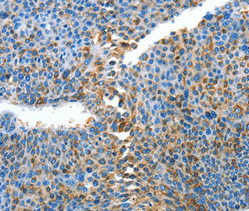

Immunohistochemical analysis of paraffin-embedded Human thyroid cancer tissue using at dilution 1/25.